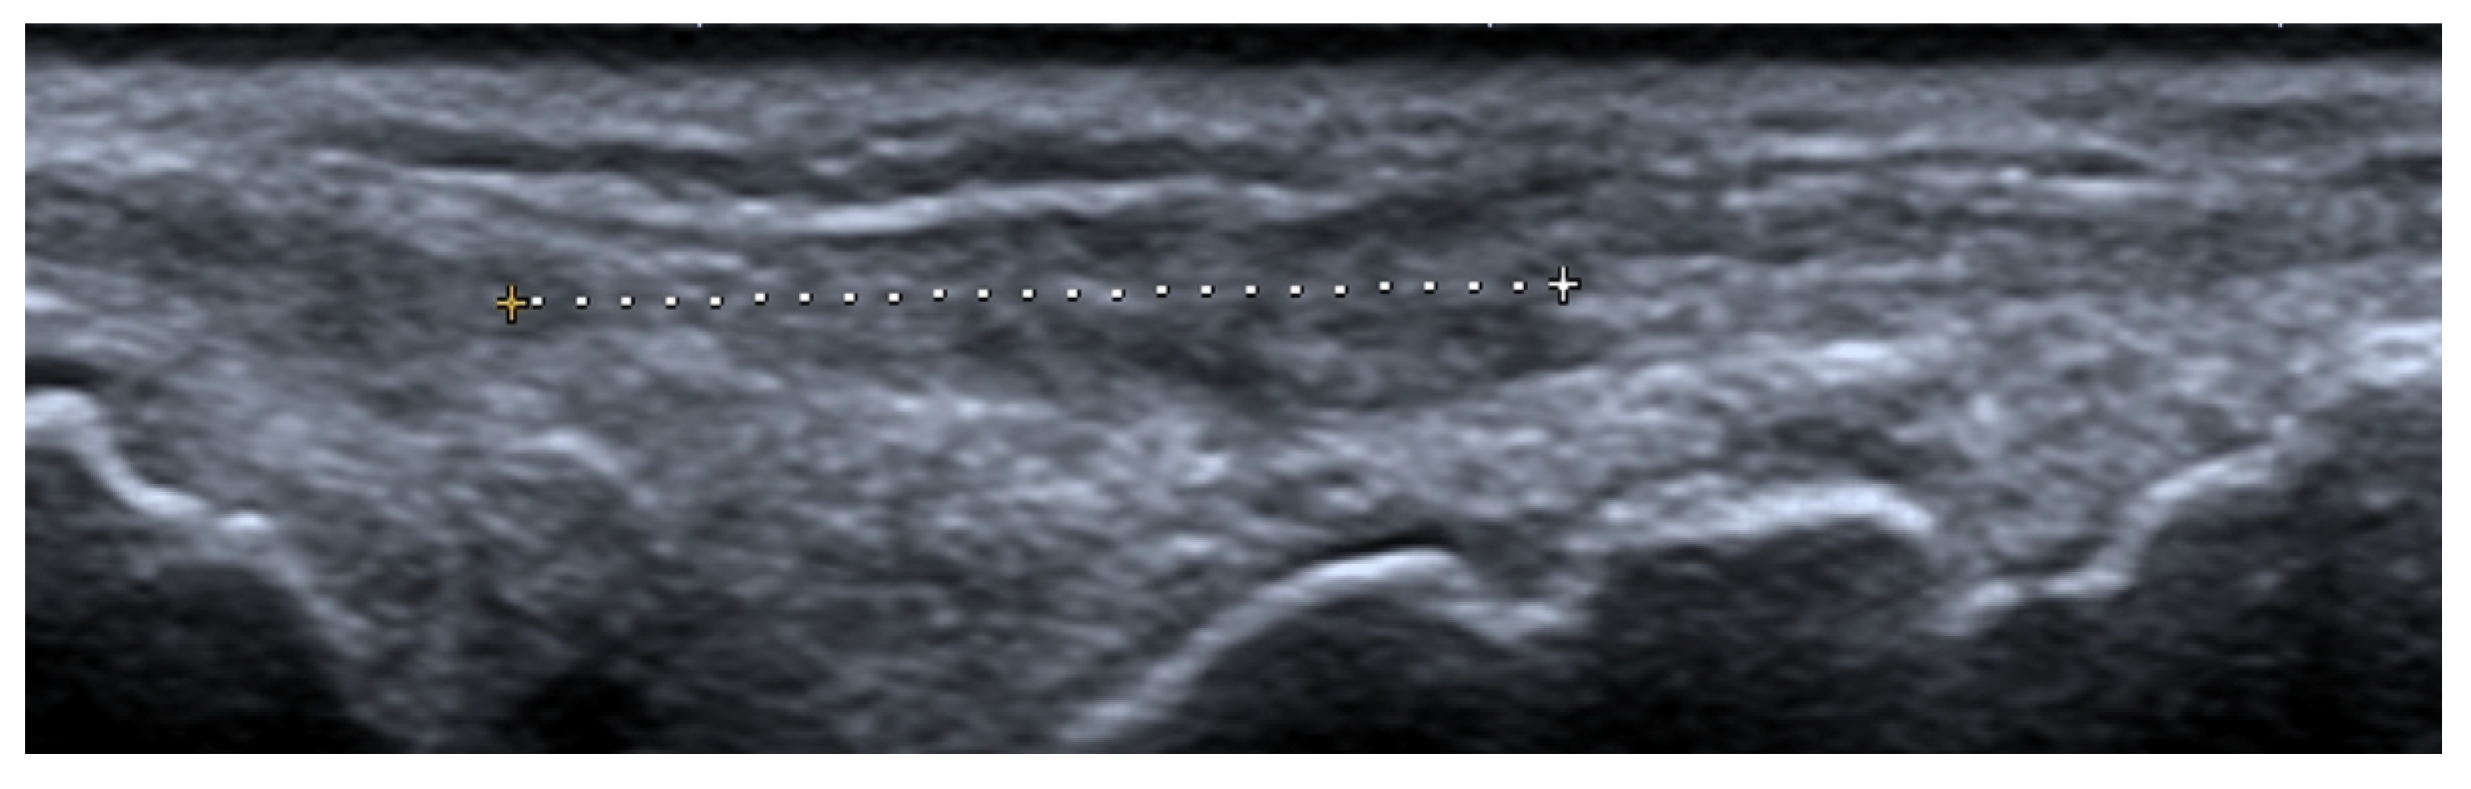

US may assist with the diagnosis and characterization of disease activity in inflammatory myopathies, with reported 82.9% sensitivity for detecting histologically proven myositis [17]. Inflammation and edema cause patchy or diffusely increased echogenicity of muscles, which may also appear swollen [17,19]. Increased vascularity on power Doppler may be seen [19]. In chronic diseases, the muscles appear atrophic with reduced volume and further increased echogenicity due to the progressive infiltration of fatty tissue [1,17,19]. In addition, by shear-wave elastography (SWE), US is able to evaluate muscle stiffness [20]. Di Matteo et al. [20] performed SWE on the quadriceps muscles in 30 SLE patients (without previous/current myositis or neuromuscular disorders) as well as 15 healthy subjects that matched the patients in age, sex, and BMI. SWE was significantly lower in SLE patients compared with the healthy subjects (1.5 m/s vs. 1.6 m/s respectively, p = 0.01).